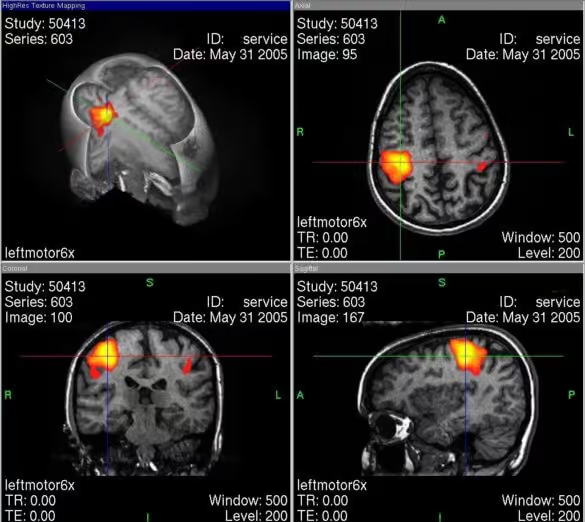

Als der Begriff „Neuromarketing“ vor rund 15 Jahren erstmals aufkam, dachten viele sofort an bunte fMRT-Bilder aus dem Labor. Damals wirkte es wie ein experimentelles Forschungsfeld, weit weg vom Tagesgeschäft. Heute hat sich das Bild komplett gewandelt. Neuromarketing ist längst kein akademisches Spielzeug mehr, sondern ein strategisches Werkzeug für Unternehmen, die Wettbewerbsvorteile systematisch aufbauen wollen.

fMRT in Aktion